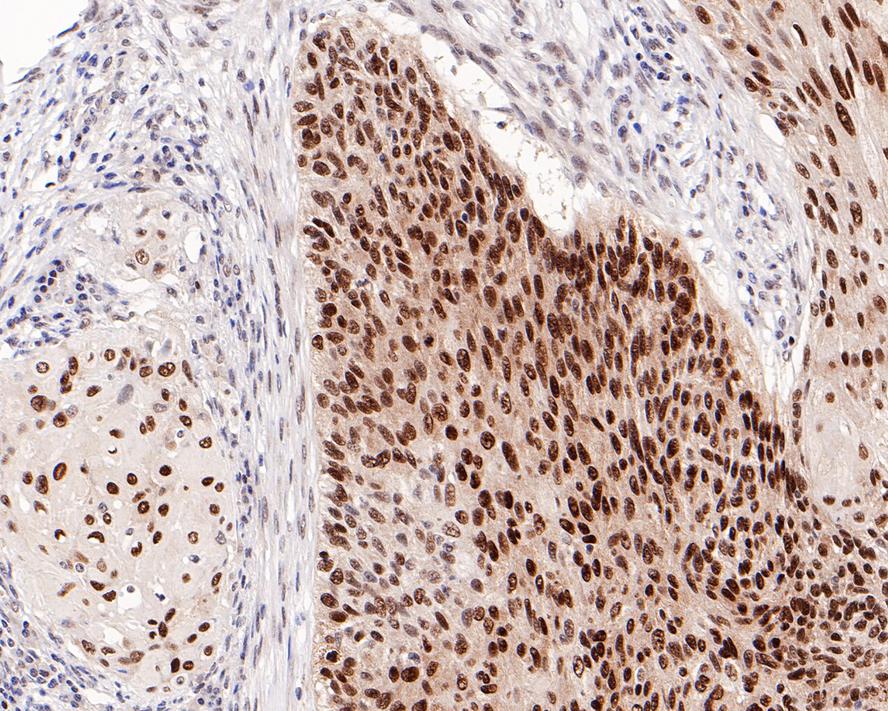

HA721155_11.jpg Fig11: Immunohistochemical analysis of paraffin-embedded human cervical carcinoma tissue with Rabbit anti-SOX2 antibody (HA721155) at 1/1,000 dilution.

The section was pre-treated using heat mediated antigen retrieval with sodium citrate buffer (pH 6.0) (high pressure) for 2 minutes. The tissues were blocked in 1% BSA for 20 minutes at room temperature, washed with ddH2O and PBS, and then probed with the primary antibody (HA721155) at 1/1,000 dilution for 1 hour at room temperature. The detection was performed using an HRP conjugated compact polymer system. DAB was used as the chromogen. Tissues were counterstained with hematoxylin and mounted with DPX.